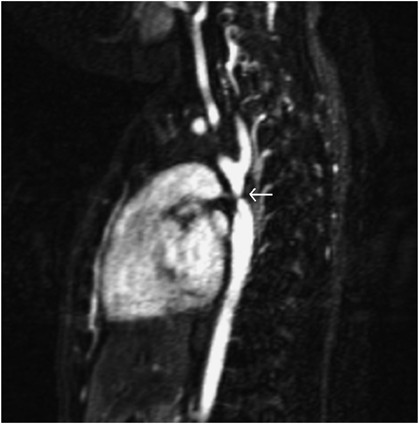

Previously reported data have suggested increased aortic stiffness17 and alteration in autonomic cardiac balance18 in pre-operative neonates with CoA, suggesting an early maladaptive response to mechanisms responsible for longer term blood pressure control (discussed below). With this in mind, we measured non-invasive indices of autonomic balance, large artery stiffness and cardiac output in an 8-month-old male with native CoA and his monozygotic twin. The index case was diagnosed following detection of systolic hypertension (130 mm Hg—95th percentile for patient's length is 104 mm Hg19) while undergoing anesthesia for assessment of airway stridor. Subsequent magnetic resonance imaging demonstrated severe CoA distal to the left subclavian artery, with several collaterals arising from the left subclavian and carotid arteries (Figure 1). Spontaneous baroreceptor reflex sensitivity (sBRS) was analyzed using sequence analysis. To evaluate sympatho-vagal balance both time domain and frequency domain indices of heart rate variability, and frequency domain analysis of blood pressure variability were performed. These assessment techniques have previously been described in detail.20 Pulse wave velocity as an indicator of large artery stiffness was measured in the right arm using a validated21 pulse volume recording technique (Vicorder, Skidmore Medical, Bristol, UK), with an inflatable cuff placed proximally and distally on the limb of interest. Cardiac output was measured non-invasively using electrical velocimetry (ICON, Osypka Medical, Berlin, Germany). This is a transthoracic bioimpedence technique that detects changes in thoracic fluid shifts based on changes in transthoracic conductivity, due to alignment of the erythrocytes during early systole, and shows excellent correlation with direct Fick estimates of cardiac output in patients with congenital heart disease.22 The measurement readings including average resting blood pressure over three recordings are listed in Table 1. Although no meaningful statistical analyses of these data can be made, it is notable that the sBRS was markedly lower in the index case suggesting dampening of the baroreceptor reflex, as demonstrated previously in infants with CoA.18 Time domain analyses of heart rate variability were higher in the control twin across all measurements (Figure 2), suggesting dominance of parasympathetic over sympathetic modulations in the control infant although wide variability may exist with these indices. Right arm pulse wave velocity values were repeatedly higher in the index case again suggesting large artery stiffness, implicated in systolic hypertension may be affected in the pre-CoA arterial bed, although it is unclear whether this is a consequence or a cause of high systolic blood pressure in this case. Repeat measurements following surgery on the index case were not carried out as continued therapy with a beta-blocker, which was required to control blood pressure, therefore acting as a confounding variable on the recorded parameters.

Contrast magnetic resonance image in the sagittal plane demonstrating the heart anteriorly and descending aortic arch and descending aorta posteriorly. Discrete coarctation of the aorta is indicated by the white arrow after the origin left subclavian artery. Numerous prominent collateral arteries providing collateral flow are seen.